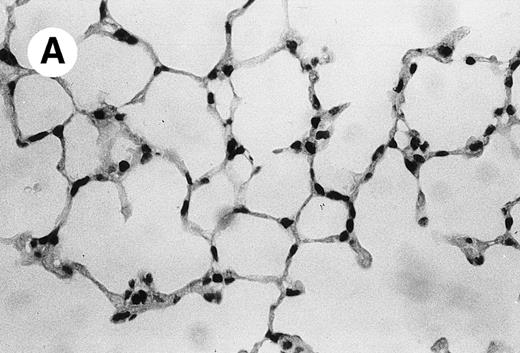

IV injection of MWReg30 caused within 15 minutes a peripheral vasodilatation, as evidenced by red extremities (tail and feet) and uncoordinated movements. These signs persisted for 60 to 90 minutes. Proportional to the injected dose of MWReg30, mice showed intestinal hemorrhages, ruffled fur, and reduced flow rate during blood sampling. Lung, kidney, and liver were sampled at different times after MWReg30 injection for histological examination. Histopathology of the whole lung performed 60 minutes after injection showed enhanced thickness of alveolar septa, due to edema and to increased cellularity, consisting of polymorphonuclear and mononuclear cell accumulation in capillaries, as compared with lungs from mice injected with PBS (Fig 4) or control IgG (not shown). This change was found to be uniform, not focal, in the two lungs (n = 6). After 24 hours, lungs showed a further enhancement of septa thickness, due to mononuclear, but not polymorphonuclear, cell accumulation in capillaries and interstitium, as well as plasma leakage into the alveolar space (Fig 4C). No changes were observed in peribronchiolar areas. As early as 20 minutes after IV injection, semithin sections showed that the vascular engorgement was essentially due to red blood cells, with very few leukocytes or platelets (Fig 4D). Twenty-four hours after injection, some mice showed centrolobular necrosis in the liver as well as glomerular shrinkage and enlargement of Bowman spaces in the kidney, compatible with hemodynamic changes of shock, but without evidence of acute tubular necrosis. Thrombi or microthrombi were not seen in any of the examined organs. Platelets recovered from the blood of mice 30 minutes after injection of MWReg30 did not express P-selectin as determined by FACS analysis. In sera from mice obtained 90 minutes after injection of MWReg30, no TNF was detectable.

Lung histopathology. Aspect of alveolar walls 60 minutes after IV injection of PBS (A) or 10 μg of MWReg30 (B); (C) 24 hours after IV injection of 10 μg of MWReg30; (D) vascular engorgement of septal capillaries with erythrocytes, 20 minutes after IV injection of 100 μg of MWReg30. (A through C) Hematoxylin/eosin staining of paraffin-embedded section (original magnification × 400). (D) Toluidine blue staining of Epoxy resin-embedded sections (original magnification × 1,000).

The lung congestion, as well as the increased cellularity of the lung septa, due to mononuclear and polymorphonuclear cells, are akin to LPS-induced lung pathology. The vascular engorgement, essentially due to erythrocytes, was more pronounced than in mice injected with 1,000 μg LPS (not shown). Histological examination showed that these changes were neither focal nor associated with atelectasis: the increased cellularity was uniform and was observed in both lungs. In contrast, control lungs from mice injected either with PBS or with normal IgG were consistently free of accumulated cells in the septa. In MWReg30-injected animals, the increased cellularity appeared to be due to cell accumulation in both vascular and interstitial compartments, although electron microscopic studies are required to clarify this point. Preliminary studies show enrichment of pinocytotic vesicles (Männel et al, manuscript in preparation). Altogether, the picture is compatible with the very early steps of acute lung injury.